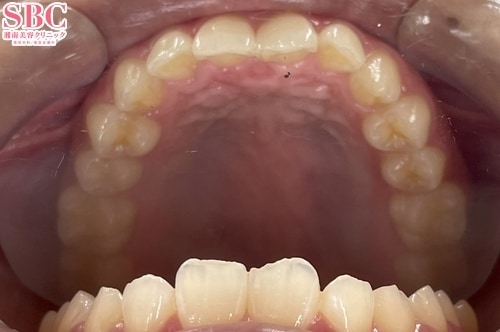

No.342030【美容歯科】ねじれている前歯を改善!

施術前

前歯中央部分にねじれがあります。

施術後10ヶ月後

アーチ上に綺麗に並びました。

インビザラインGOの症例です。

20枚のマウスピースで美しくなられました。